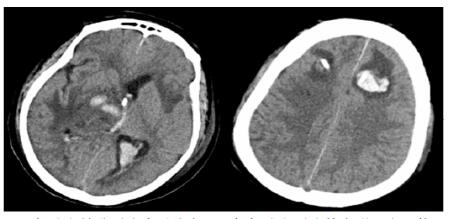

转入ICU后呼吸机辅助通气、甘露醇100 mL/8 h静滴脱水、头孢呋辛1.5 g/12 h静滴抗感染,肠内营养等支持治疗。当晚血常规:白细胞13.3×109/L,中性粒细胞百分比85.3%,C反应蛋白17.1 mg/L,降钙素原0.64 ng/mL。脑室外引流术后次日血化验:白细胞16.6×109/L,中性粒细胞百分比92.8%,C反应蛋白78.4 mg/L;从脑室外引流管留取脑脊液检验:有核细胞6×106/L,红细胞1 960×106/L,蛋白含量1.717 g/L,葡萄糖4.72 mmol/L,细菌培养阴性,涂片未找到细菌;复查头颅CT示:脑室扩张好转,右侧丘脑、左侧岛叶病变伴出血(图 2);胸部CT示,两肺间质性肺炎下叶为著,较前(2019年6月21日)部分好转(图 3)。考虑到炎症指标升高,遂改哌拉西林他唑巴坦3.375 g/12 h静滴抗感染。此后经脑室外引流管反复留取脑脊液送检涂片及培养均阴性。术后第5天行“导航下立体定向颅内病灶活检术+双侧omaya囊置入术”,术中穿刺液呈黄色黏稠脓性,考虑脑脓肿,留取脓液送高通量测序(next-generation sequencing, NGS),并升级为美罗培南2 g/8 h联合利奈唑胺0.6 g/12 h静滴抗感染治疗。术后第7天患者突发血压升高、瞳孔不等大,昏迷程度加深;急查头颅CT示,双侧脑室钻孔引流术后改变,双侧侧脑室引流管走形区出血伴血肿形成;右侧丘脑区积液、积血,双侧脑室积血新发(图 4),甘露醇加量至250 mL/8 h联合地塞米松5 mg/6 h静滴加强脱水;当日术中脓液高通量测序结果回报:皮疽诺卡菌(序列数52 867个)、支气管戈登菌(序列数10个)。确诊脑诺卡菌病,抗菌治疗方案改为亚胺培南西司他丁0.5 g/6 h静滴,联合利奈唑胺0.6 g/12 h和复方磺胺甲恶唑片(0.48 g/片)3片/6 h口服。此后患者仍伴低热,炎症指标呈上升趋势。术后2周患者再次突发血压升高、瞳孔不等大、对光反射消失、神志深昏迷,急查头颅CT示再发脑疝(图 5),急诊行“去骨瓣减压术+脑内血肿清除术”,术后患者仍呈深昏迷状态,双侧瞳孔散大、对光反射消失,次日自动出院。

| 双侧脑室钻孔引流术后改变,双侧侧脑室引流管走形区出血伴血肿形成;右侧丘脑区积液、积血,双侧脑室积血新发 图 4 患者2019-10-06头颅CT结果 |

| 双侧侧脑室引流管走形区出血伴血肿形成;右侧丘脑区积液、积血,脑室积血;左引流管旁血肿较前(2019-10-06)增大,脑室积血增多,中线右移。左岛叶及颞叶斑块状低密度影 图 5 患者2019-10-13头颅CT平扫结果 |